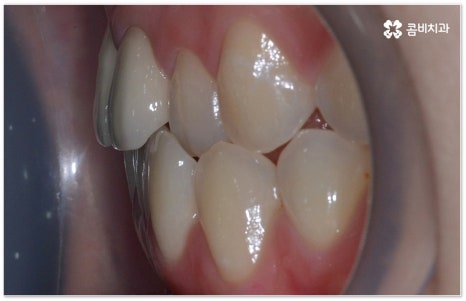

부정교합을 개선할 때 교합이 어긋난 정도가 심하고 구조적인 원인이 커서 부분 교정이 아닌 전체 교정이 필요한 케이스인 경우라고 해도 말씀드렸던 클리피씨 교정 장치 또는 보다 심미성을 강조한 치아교정장치 들의 도움을 통해 다른 사람과 얘기를 하거나 음식을 먹을 때 브라켓이 두드러지게 드러나는 부담을 줄일 수 있으니 설측교정, 콤비교정, 투명교정, 인비절라인 등에 대해서 한 번 알아보시고 각자에게 맞는 방법으로 교정 치료를 시작해 보시길 권유드리고 있어요.

특히 투명교정의 경우 겉에서 봤을 때 교정하는 티가 거의 나지 않는 특수 플라스틱을 이용한 장치이기 때문에 심미적으로 보다 만족스러울 수 있는데요. 브라켓이나 와이어가 없으므로 이물감이 적고 이로 인해 입 안 쪽에 상처가 발생하지도 않게 되며, 발음도 명확하게 구사할 수 있다는 장점 또한 가지고 있어요. 식사할 때 빼놨다가 양치 후 닦아서 다시 끼면 되기 때문에 관리할 때도 용이하지만 이러한 탈착식 장치는 착용하는 시간을 어느 정도 확보해야 보다 효과적인 치료 결과가 나올 수 있다는 점을 명심하고 환자분들 스스로 정해진 시간 이상 잘 착용해 주실 필요가 있습니다. 치아가 얼마나 이동했는가를 보고 환자분들의 상황에 맞게 그때 그때 본을 떠서 치아교정장치 를 제작하기 때문에 섬세한 진행이 가능하다는 장점이 있으나 빠르고 정확하게 대응을 하기 위해서 다양한 케이스를 다뤄보신 노하우가 있는 선생님과 함께 하시는 것이 무엇보다 중요하다는 점 또한 잘 알아두시면 좋을 거예요.